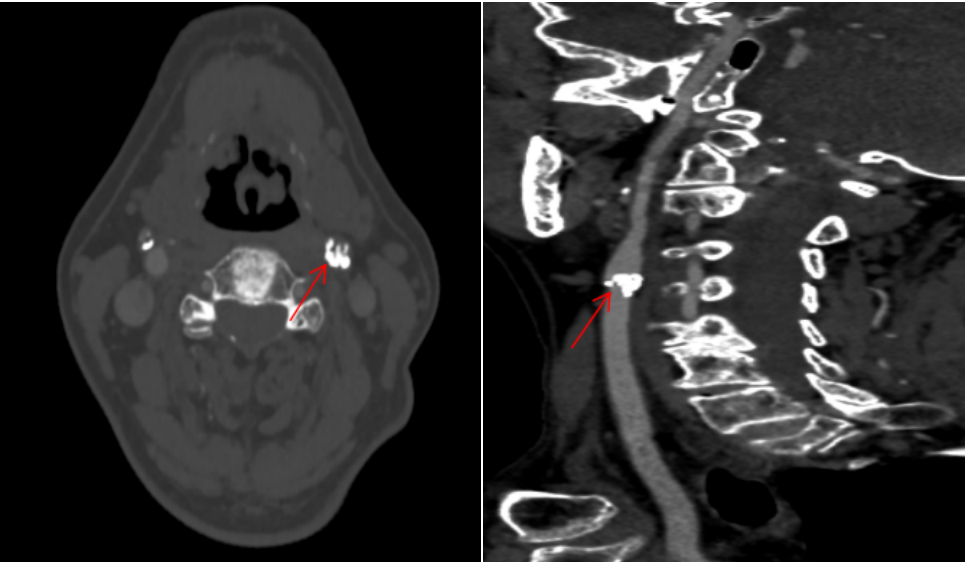

经头颅 CTA、全脑血管造影等检查,发现刘大爷左侧颈动脉窦部出现严重环形钙化斑块,已造成血管重度狭窄,导致同侧大脑供血严重不足,只能依靠对侧颈内动脉通过前交通动脉向左侧大脑中动脉部分代偿供血。